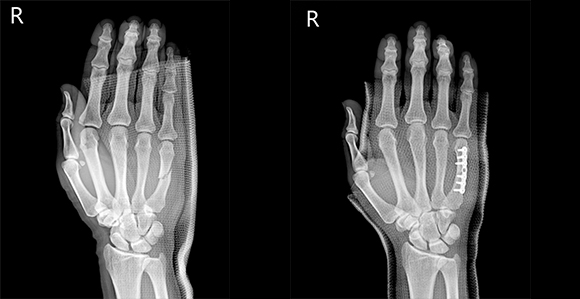

관혈적 정복이란 골절된 부위를 절개하고 뼈를 노출시켜 눈으로 직접 보면서 골절편을 정확하게 맞추는 방법으로 금속판과 나사 고정법, 핀고정법, 나사고정법, 골수 내정 고정법, 인공 관절 치환술, 외고정 기구 고정법 등등 여러 방식이 있습니다.

- 콜레스 골절, 복서 골절